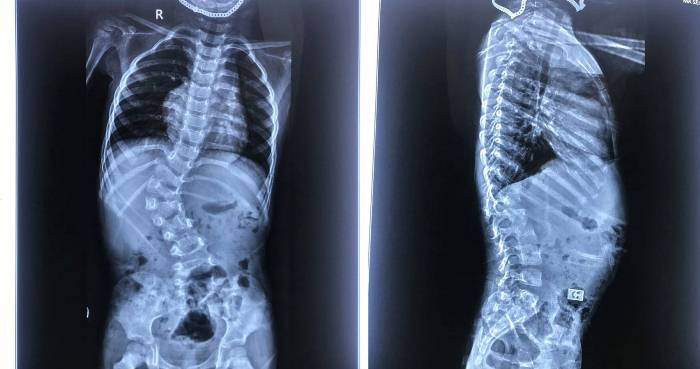

Hình ảnh phim chụp cột sống bệnh nhi B.Đ bị vẹo ngực – thắt lưng bẩm sinh mức độ lớn do dị tật nửa đốt sống L1 trước khi mổ.

Hình ảnh phim chụp cột sống bệnh nhi B.Đ sau khi mổ, đã được nắn chỉnh vẹo cột sống.

BS.Nguyễn Duy Thụy, nhận định: Bệnh nhi B.Đ là trường hợp đặc biệt vì nhỏ tuổi, nhưng đã có biến dạng cột sống rất lớn, góc vẹo cột sống T11-L2 66 độ, có dị tật nửa thân đốt L1 bên phải, thiểu sản cuống sống T12 bên phải. Do vậy, tính chất cuộc phẫu thuật rất phức tạp.

Hiện nay, cháu B.Đ đang tập ngồi và đi lại được, tiểu tự chủ. Hình ảnh X. quang sau mổ cho thấy biến dạng được nắn chỉnh rất tốt, giữ được chức năng 3 đĩa đệm cuối cùng của cột sống thắt lưng.